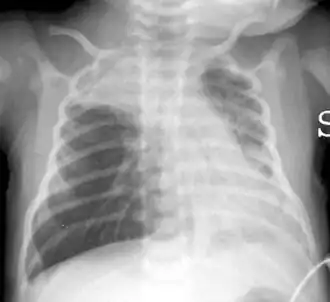

![]() Rayos X de tórax mostrando hiperinflación con diafragma aplanado y atelectasias bilaterales en un recién nacido de 16 días. | ||

En un caso típico, la bronquiolitis se presenta en un niño menor de dos años quien presenta un cuadro agudo de obstrucción de las vías respiratorias inferiores, caracterizado por tos, silbidos en el pecho, crepitantes, subcrepitantes y respiración entrecortada y rápida de varios días de evolución, habitualmente precedido de sintomatología respiratoria de las vías altas (como un resfriado común).[2] Otros síntomas incluyen piel azulada por falta de oxígeno, falta de respiración o dificultad respiratoria, fiebre, tiraje intercostal y aleteo nasal en bebés.[13] Los datos radiológicos pueden mostrar atrapamiento aéreo y aplanamiento de los arcos costales.[19]